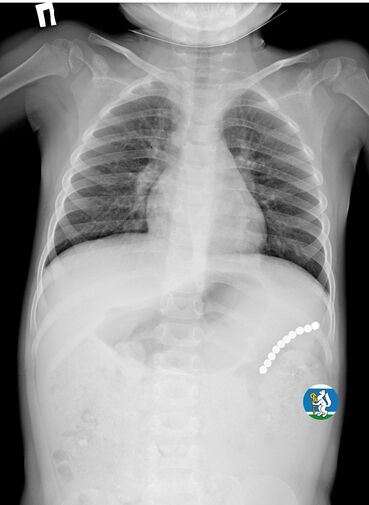

Девочка рассказала родителям о плохом самочувствии, и те показали ее врачам. Медики направили пациентку на рентген грудной клетки. Благодаря обследованию специалисты обнаружили в проекции желудка цепочку магнитов, соединенных между собой. Ребенку сразу же госпитализировали и оказали помощь.

«Для минимизации риска осложнений удаление инородных тел было проведено интраоперационно. В ходе вмешательства дежурная бригада врачей извлекла 10 магнитных шариков, цепочка которых в длину составила 5 сантиметров», — рассказал детский хирург ДГКБ №9 Андрей Чукреев.